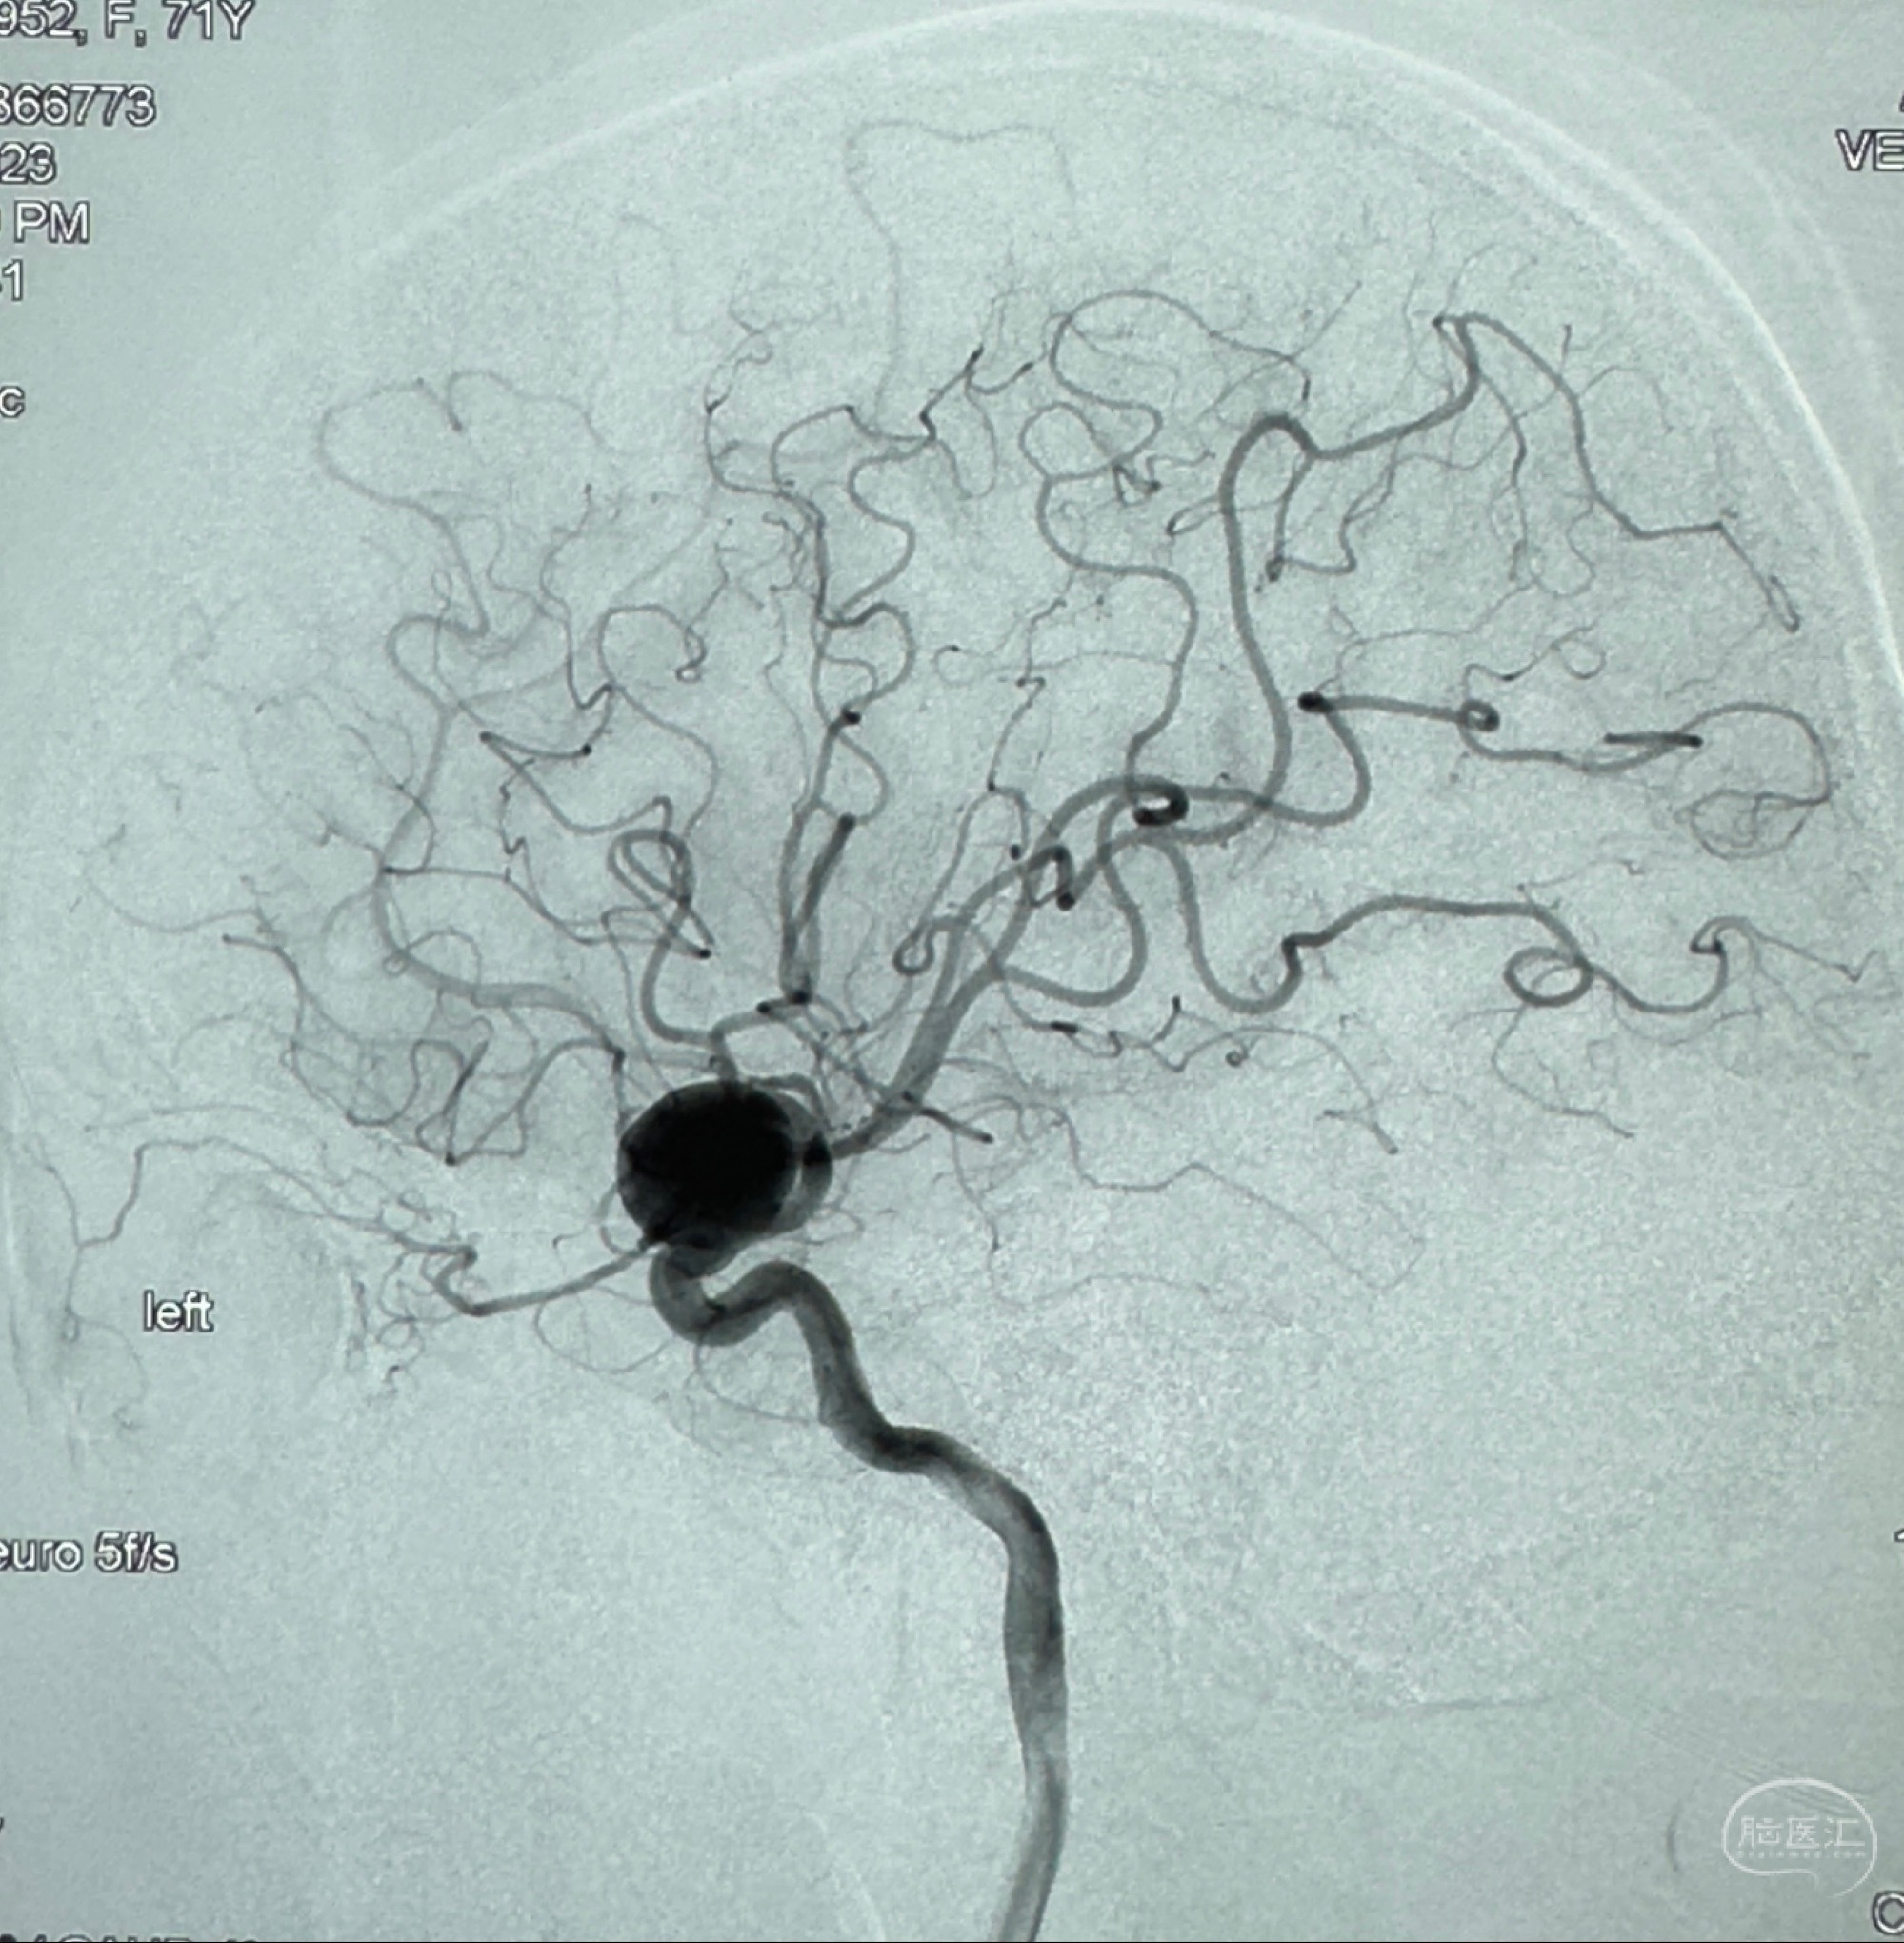

2023-12-27术后第十天复查DSA

支架贴壁佳,但可见射流,咋办?

2024-01-08全麻下再行植入密网支架一枚

Tubridge 4.5-35mm

支架植入顺利,贴壁佳,支架内血流通畅,动脉瘤内血液滞留明显